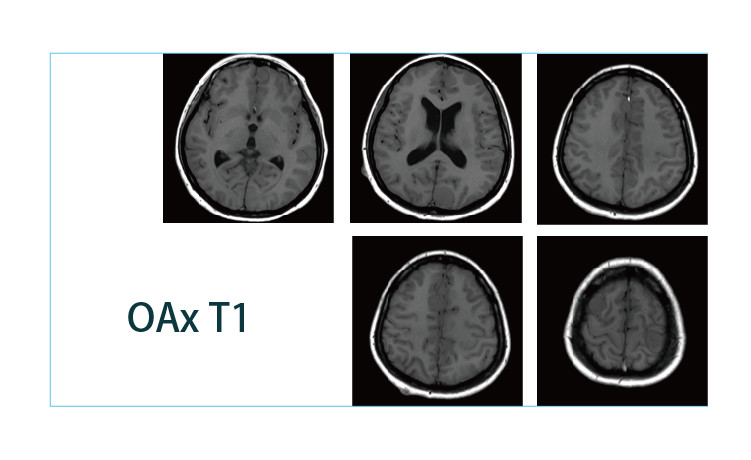

【朗润影像档案】20190412磁共振影像病例结果讨论